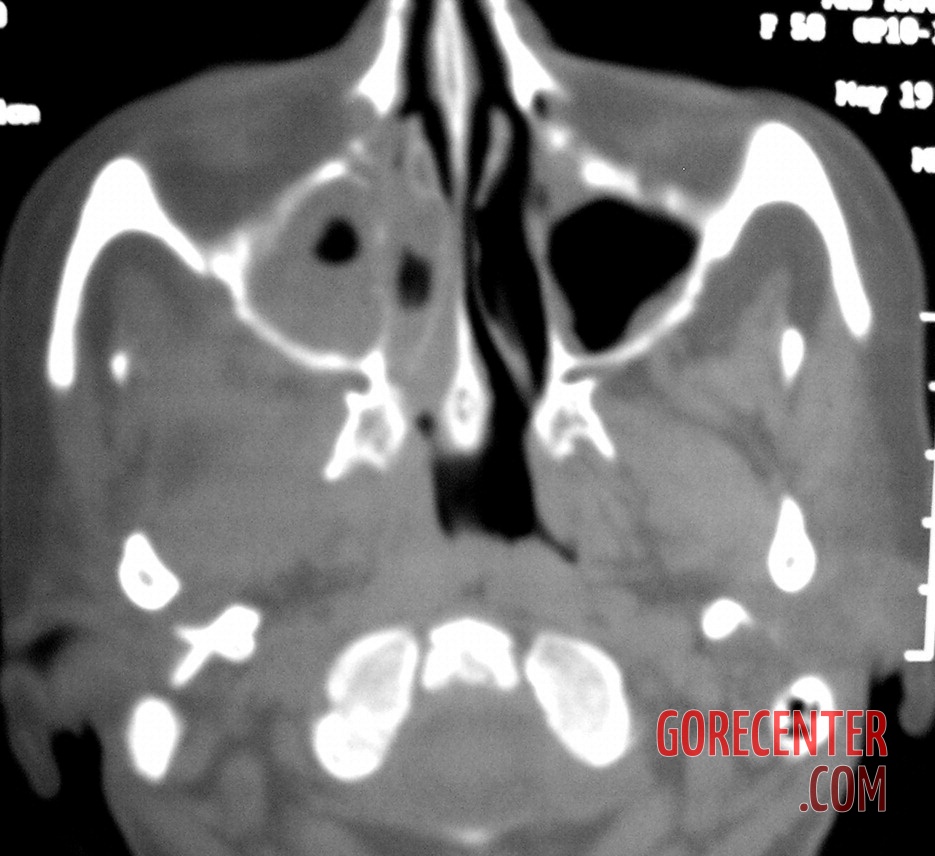

During examination, doctors found an extensive area of dead tissue in the right upper jaw. The damage extended from the canine tooth backward beyond the last part of the jaw, toward the midline of the palate and into the gum area. The surrounding mucosa appeared relatively normal at first glance, which was deceptive. On palpation, the maxillary sinus area was also painful, and signs of inflammation and a small amount of pus were present in the right nasal cavity.

Further examinations, including blood tests, did not reveal diabetes or other common conditions that could explain the symptoms. However, it was evident that the body was fighting a severe infection. A crucial turning point came with a CT scan, which revealed extensive damage to the maxillary bone and spread of inflammation into the paranasal sinuses, including the deeper ones. Fortunately, the brain and eye sockets were not yet affected.